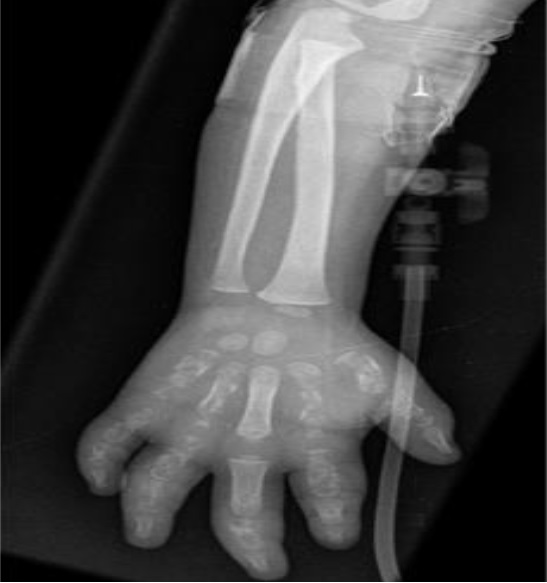

Em ultrassonografia de membros inferiores, foram confirmados abscessos nos pés. Na investigação, foi diagnosticada a osteomielite que acometia úmero, tíbia, ossos dos pés e das mãos bilateralmente. Foi feita drenagem contínua de lojas de secreção purulenta na região das tíbias.

As radiografias confirmaram o diagnóstico de osteomielite (Figuras 1 a 5). Em culturas de secreção tibial, foram isolados Escherichia coliESBL e Proteus mirabilis, sensíveis a imipenem e amicacina. Dessa forma, optou-se por tratamento com antibioticoterapia parenteral, ao longo de tempo prolongado de internação.

Foram realizadas radiografias seriadas e o consequente tratamento cirúrgico de drenagem de abscessos e colocação de drenos. Não foram realizadas cintilografias e ressonância magnética, uma vez que o diagnóstico se fez tardiamente com o quadro já instalado de forma importante. Esses últimos exames contribuiriam para um diagnóstico mais precoce. Não foi realizada biópsia óssea das áreas acometidas, exame eventualmente necessário1. Em alguns casos, radiografias podem estar normais4, porém, em outros, como no caso descrito, elas se apresentam alteradas, conforme visto nas imagens.

Em seguimento ambulatorial, o paciente apresenta padrão radiológico melhor, como evidenciado em radiografia recente, ausente o atraso no crescimento, uma vez que placas epifisárias não se mostram afetadas. Permaneceu em antibioticoterapia estendida por mais cinco meses além do programado na alta hospitalar e isento de complicações novas por osteomielite. Internações devido às crises álgicas ou outros tipos de infecções já foram registradas.